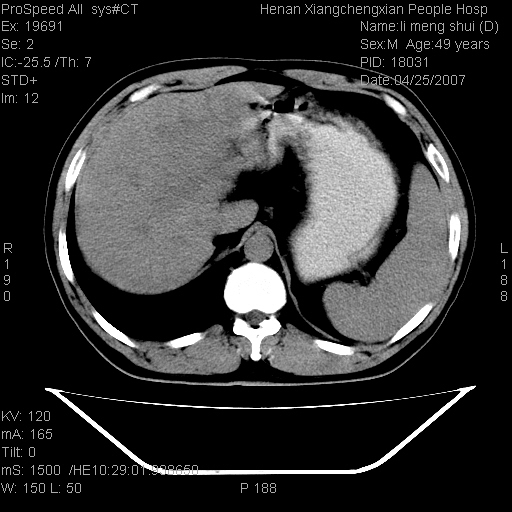

| 患者,男,49岁, 腹疼伴恶心\\呕吐20天,20天前无明显诱因出现右上腹部疼痛,钝疼,无放射,伴恶心\\呕吐,不伴发热.患者不愿增强. b超:肝脏右叶实性占位. ct:肝脏右叶可见一巨块状圆形低密度影,大小约93mm*84mm,其内可见点状高密度影,胆囊、胰腺、脾脏大小、形态及密度未见异常,腹膜后间隙未见肿大淋巴结影。 印象:肝脏右叶巨大肿块,性质待定,建议增强并穿刺活检进一步确诊。 ct平扫: ![]() ![]() ![]() ![]() ![]() ![]() ![]() ![]() ![]() ![]() ![]() ![]() ![]() ![]() ![]() ![]() ![]() 肝脏右叶肿块ct引导下穿刺活检术 患者于16时05分仰卧于ct检查台上,首先行肝脏ct扫描确定进针位置、深度、角度。在局麻下行ct引导下肝脏右叶肿块穿刺活检术。常规消毒、铺巾、局麻。在ct引导下使活检针经右侧腋中线、第9肋间隙垂直胸壁进针90mm,针头进入病变预定位置。在病变预定位置多点、多方向抽取小米样病变组织多块,涂片五张送病理检查。术后穿刺点局部无出血,未出现腹腔积液等并发症。术中及术后患者生命体征稳定,手术于17时10分成功完成。患者安返病房。 穿刺片 ![]() ![]() ![]() ![]() ![]() ![]() ![]() ![]() ![]() ![]() ![]() ![]() ![]() ![]() ![]() ![]() 病理结果肝细胞癌 ![]() 原贴地址:http://www.radinet.com.cn/forum_view.asp?forum_id=4&view_id=24130 ok |